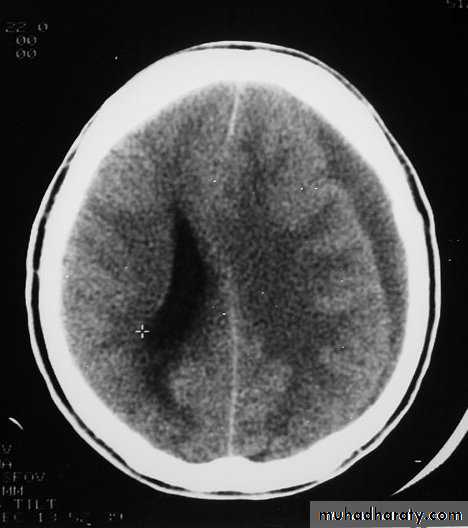

CT scan: the acute clotted blood is initially appears white (hyperdence), but as it liquefies, it slowly becomes black (hypodense).

Chronic Subdural Haematoma